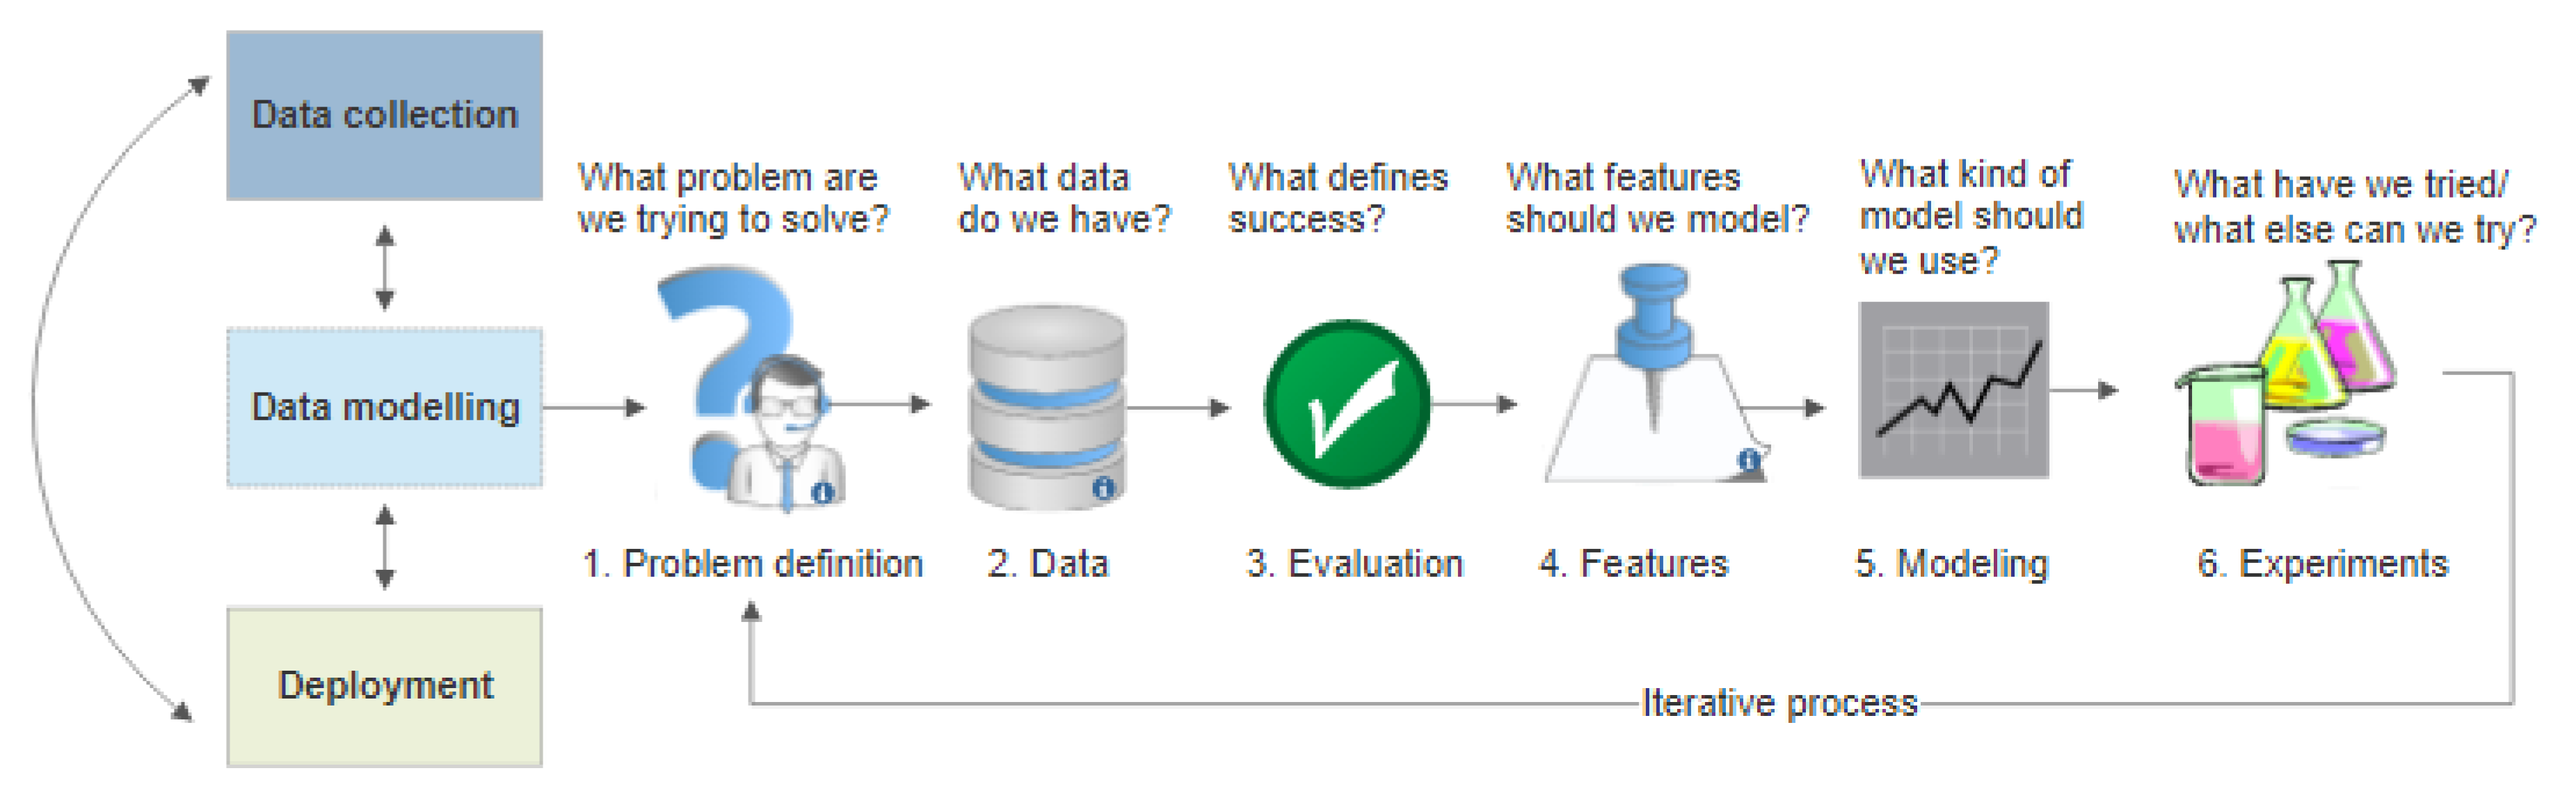

4. Machine Learning

6. Literature Review